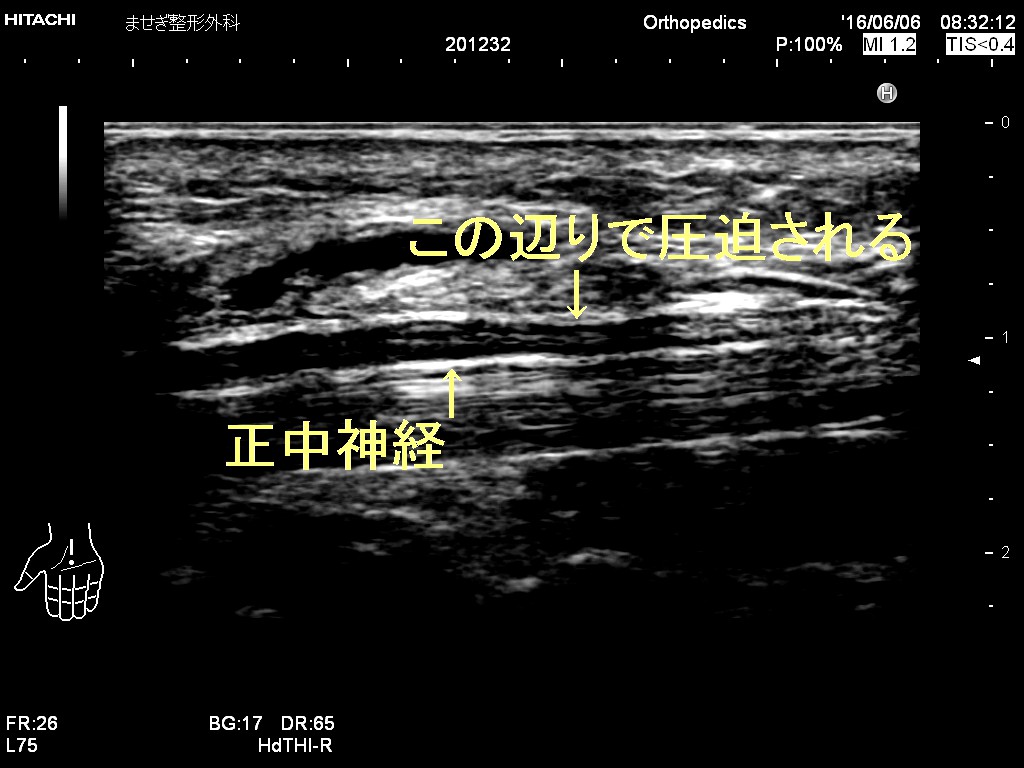

ところがここでもエコーが活躍できるのです。麻痺の原因の正中神経は

腋から手首までほとんどの領域で観察可能なのです。

以下がエコー画像です。

正常像です。ぶつぶつしたブドウの房状のものが

神経です

神経はやや腫大しその下にある腱周囲が黒く腫れています

慣れれば簡単です。

エコーで観察し神経の圧迫がないかまた神経の腫瘍がないかも

わかることが多いです。